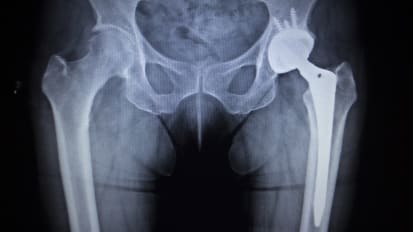

HIV patients can safely undergo hip replacement, study finds News

HIV patients can safely undergo hip replacement, study finds

UTSW researchers see no increased risk of complications following total hip arthroplasty